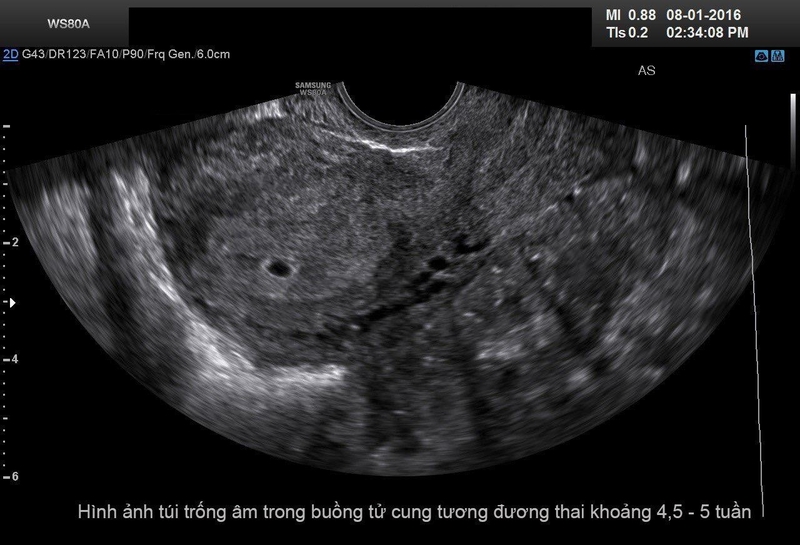

Thông thường, vào khoảng tuần thứ 5 – 6 của thai kỳ, trứng đã thụ tinh sẽ có phôi thai và túi thai, chiều rộng khoảng 18mm. Tuy nhiên, nếu trường hợp thai trứng trống xảy ra, túi thai vẫn hình thành và phát triển bình thường, nhưng siêu âm sẽ không có phôi thai.

Trên thực tế, không phải trường hợp xuất huyết nào trong 3 tháng đầu thai kỳ cũng đều là biểu hiện sảy thai. Do đó, không có dấu hiệu chính xác nhận biết mang thai trứng trống ngoài việc bạn tìm đến gặp bác sĩ để được siêu âm và thăm khám chuẩn xác. Và để chẩn đoán có phải mang thai trứng trống hay không còn phải dựa trên hình ảnh siêu âm để thấy tử cung rỗng hoặc túi thai trống.

Bác sĩ sẽ yêu cầu thai phụ tiến hành siêu âm như bình thường. Vào thời gian đầu của thai kỳ, siêu âm sẽ thấy có túi thai kích thước từ 19 – 36 mm nhưng chưa thấy phôi thai. Nếu lần siêu âm sau vào tuần thứ 8 – 13 mà vẫn chưa thấy phôi thai thì có thể kết luận là thai bất thường, mang thai trứng trống.